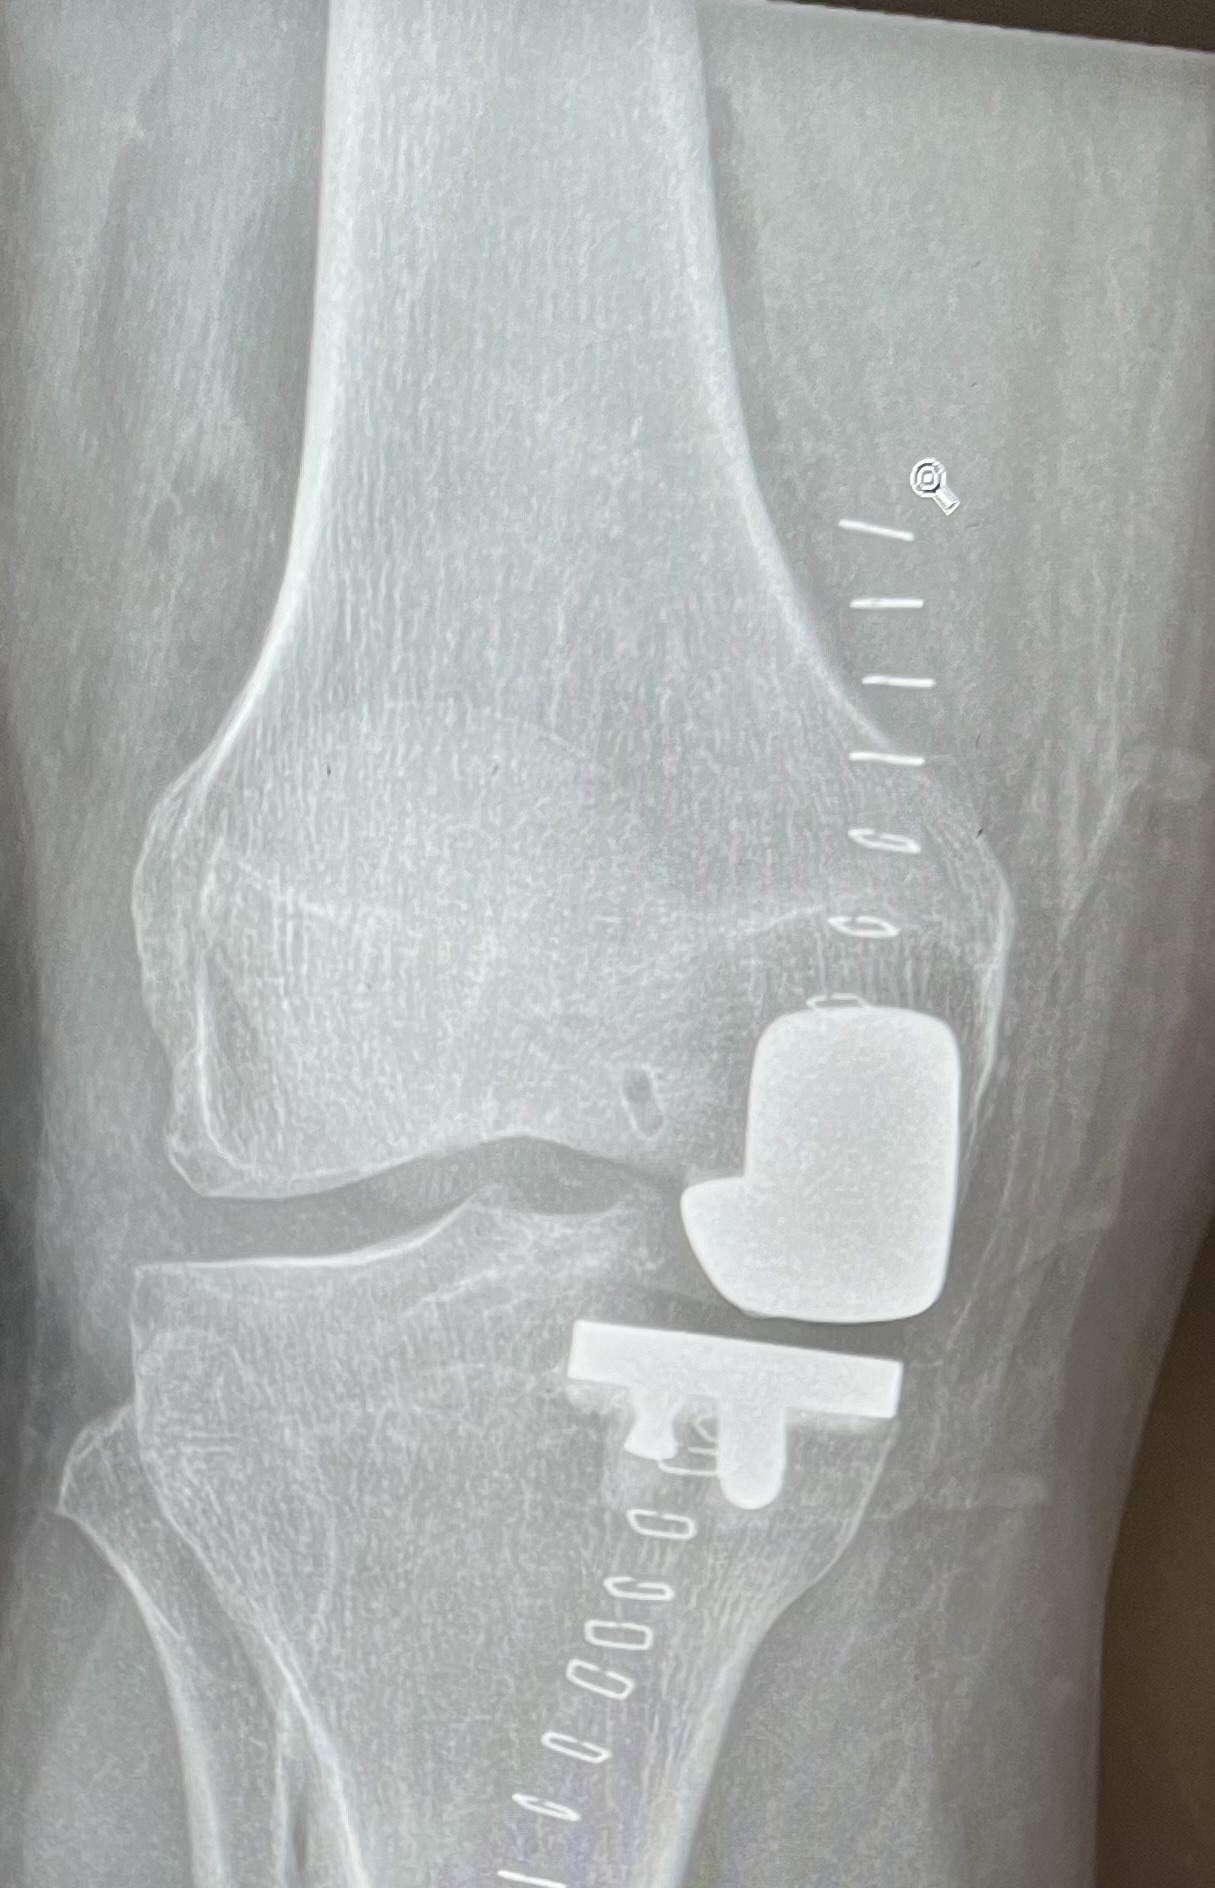

Then disaster struck when I tore my medial meniscus cartilage and discovered serious bone wear either side of it. After a minor surgery to try and sort the cartilage out it was obvious that I was going to need a knee replacement.

After several months of hobbling around and, in the end, being unable to walk more than 200m, the knee got replaced.